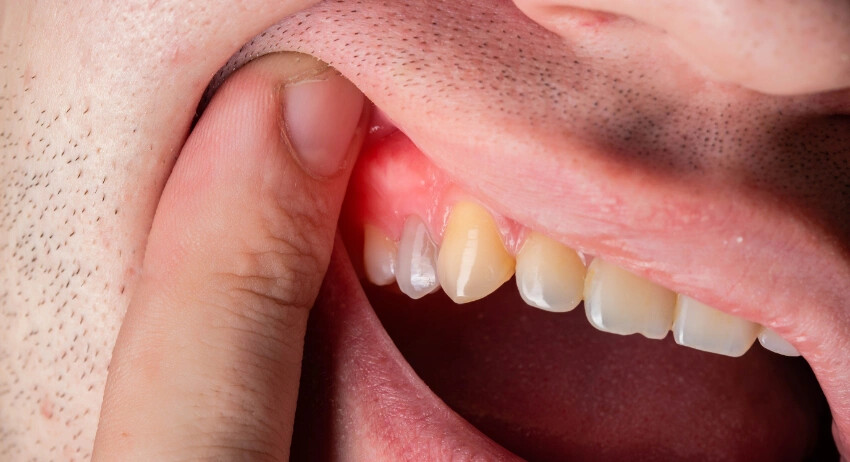

Gingivitis (Gum Disease)

Gingivitis (Gum Disease) is an earlier stage of gum disease that is caused by the bacterial infection where the plaque is built up around the gum lines. Common symptoms of Gingivitis are tooth sensitivity, tooth pain and the bleeding while brushing.

When Does Gingivitis Need a Dentist?

Once the plaque is already formed and you may observe pain and blood while brushing, it’s time to get treated by a dentist for dental cleaning benefits; Otherwise, it may proceed to its second stage – periodontitis.